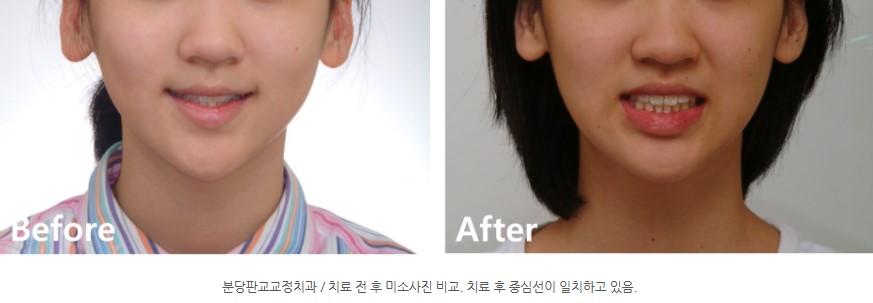

정면 미소에서도 치열의 좌우 밸런스가 좋아졌고,

송곳니가 제자리를 찾으면서 자연스럽고 조화로운 스마일 라인이 완성되었습니다.